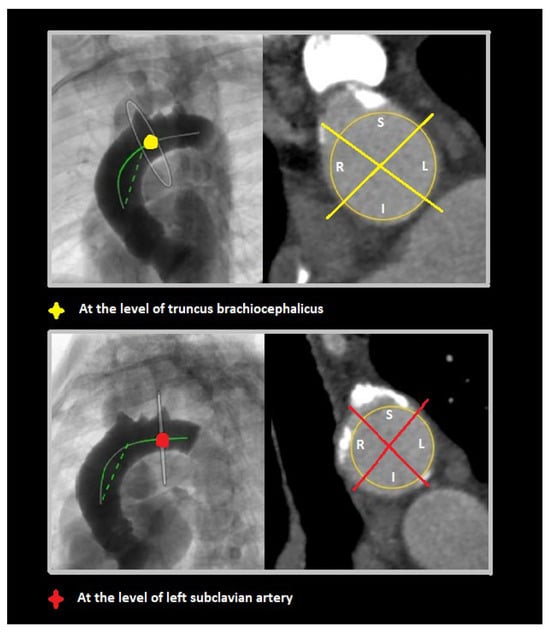

- (2)

- Middle segment, from mid-ascending aorta (at pulmonary artery bifurcation) to origin of brachiocephalic trunk;

- (3)

- Distal segment, from origin of brachiocephalic trunk to origin of left subclavian artery.